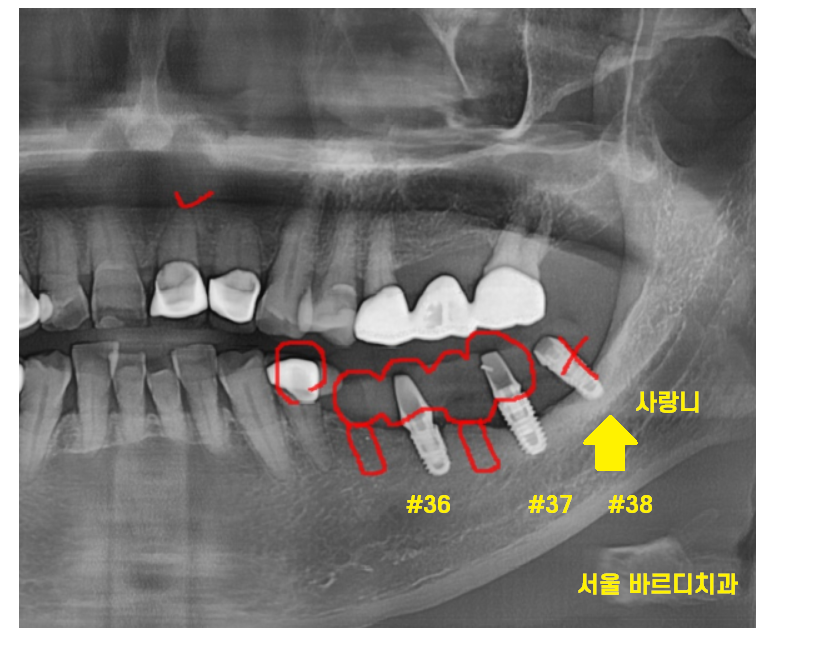

사랑니에 심어져있던 임플란트는

각도도 좋지 않고

뼈도 많이 녹아서 발치

앞쪽에 있는 임플란트는 뼈가

녹지 않아서 그대로 살려서 쓰기로 결정했습니다.

대신에 중간중간 새로운 임플란트를 심어

튼튼하게 보강은 필요했습니다.

이가 부서진 부위를 제거하고 나면

빈 공간이 생기는데

이 부분을 메꿀 필요가 있었기 때문입니다.